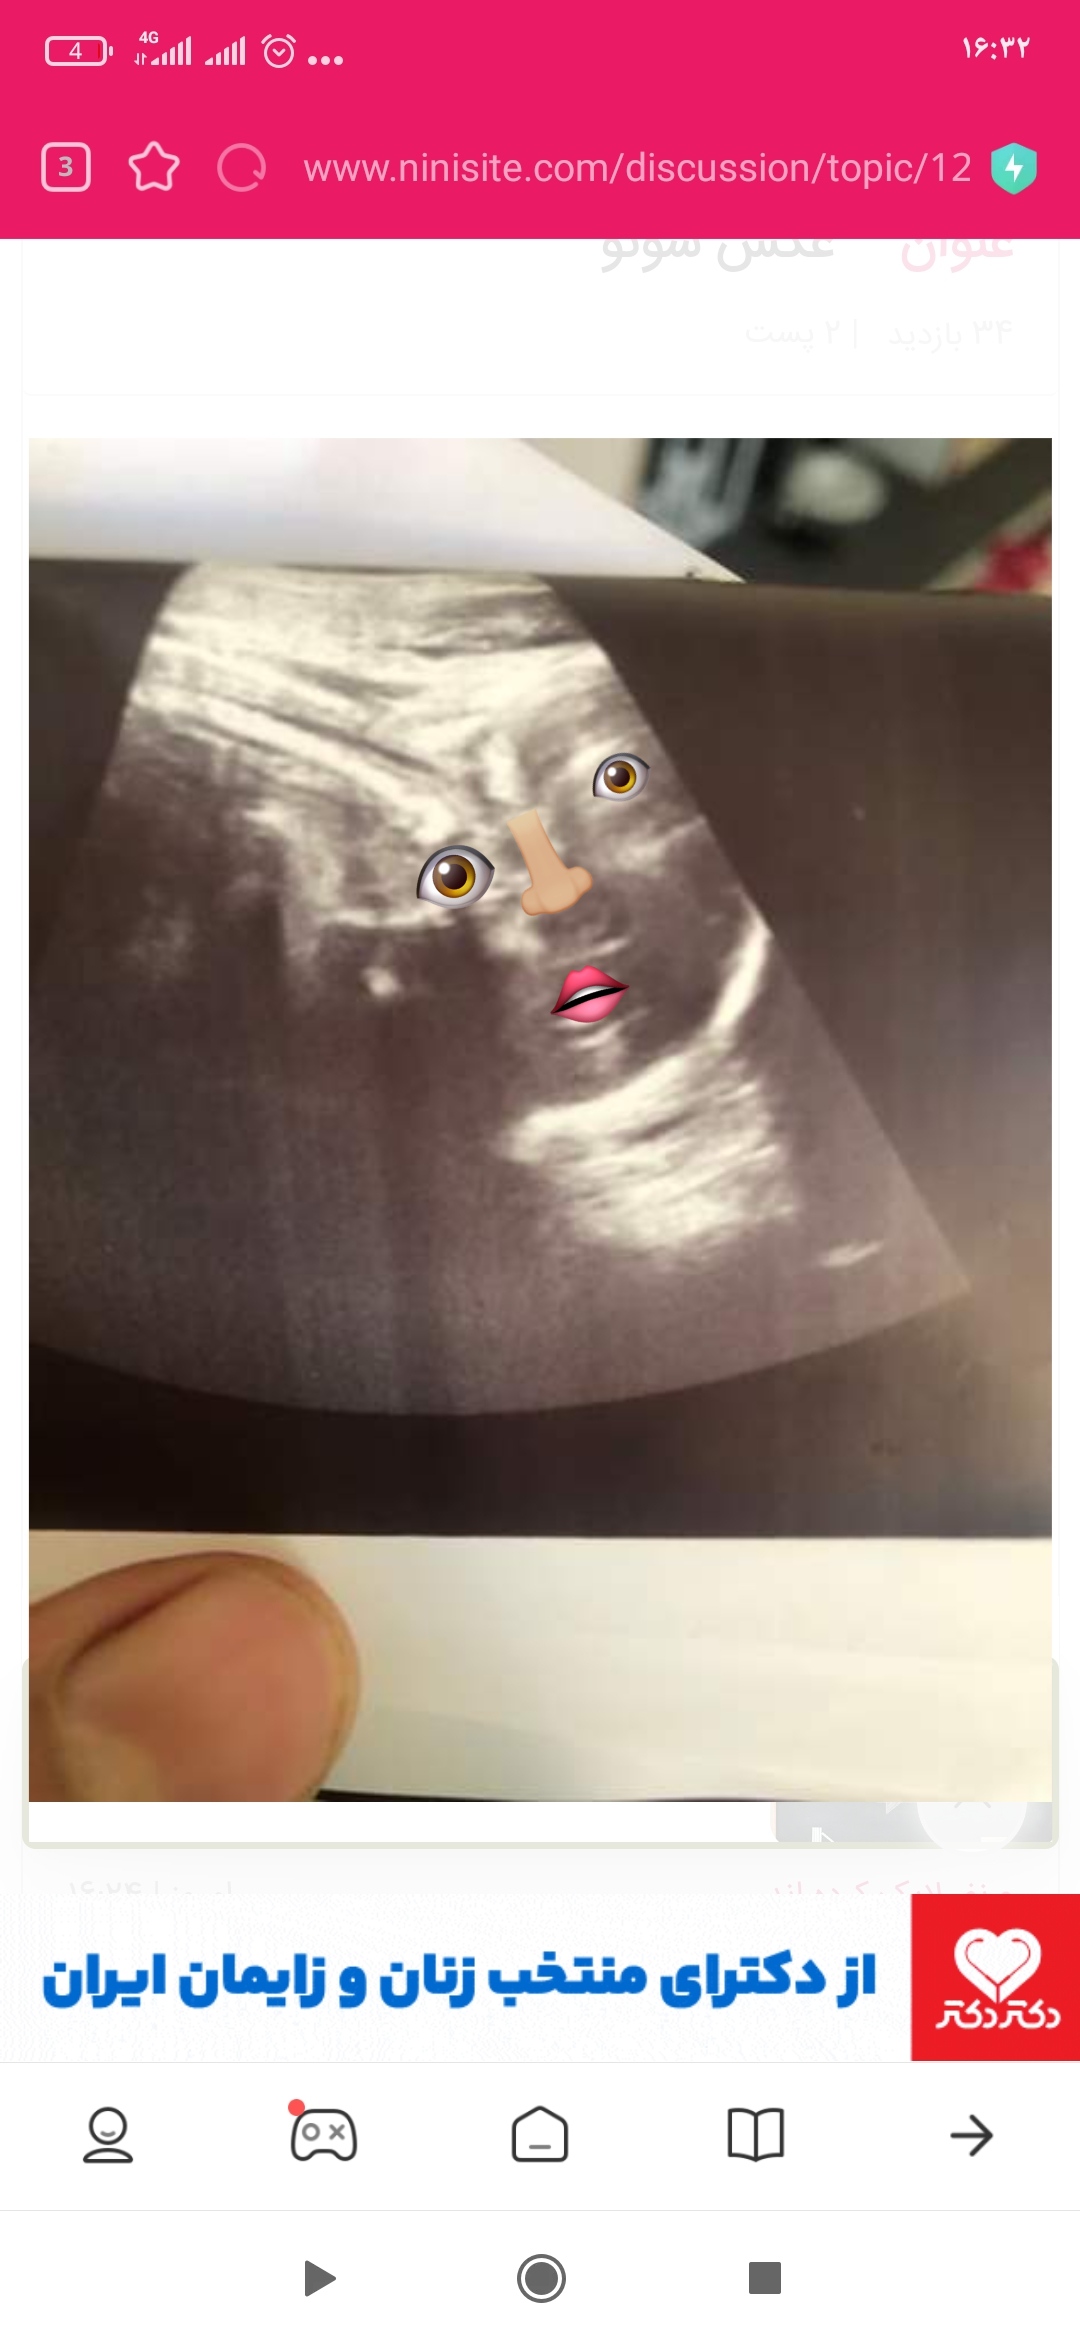

nasiiiim1373 مدیر استارتر عضویت: 1402/01/28 تعداد پست: 567 عنوان عکس سونو 145 بازدید | 7 پست سلام بچه ها،،کسی میتونه تشخیص بده این عکس ایا صورت جنینه یا نه؟؟از روبرو...این عکس مال ۳۰ هفته س..و میگفتن ک فقط صورتش مشخصه..این گردیه صورتشه ؟؟؟ 1402/09/09 | 16:24 0 نفر لایک کرده اند ... گزارش تاپیک نامناسب

nasiiiim1373 مدیر استارتر عضویت: 1402/01/28 تعداد پست: 567 من دستاشم میبینم🥺🥺🥺 الان این عکس کجاشه؟؟؟اصن صورتش هس یا نه؟؟اون مشکی پایین دهنشه بازه؟

zoleykhabano عضویت: 1401/07/27 تعداد پست: 5798 ببخشید اینجوری اشکال رو گذاشتم تا بفهمی برا مادر شدنم دعا کنین🙏

nasiiiim1373 مدیر استارتر عضویت: 1402/01/28 تعداد پست: 567 منم همینو میبینم،پس صورتشه!!!؟الهی قربونش برم🥺شما سر درمیاری از عکس سونو یا همینجوری مث من میبینی!؟

zoleykhabano عضویت: 1401/07/27 تعداد پست: 5798 ن منم مثل شما میبینم خدا حفظش کنه عشقووووو برا مادر شدنم دعا کنین🙏